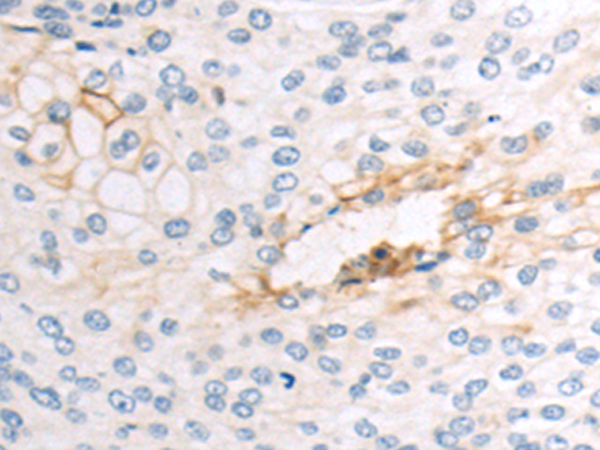

分类: 科研抗体货号: P00274别名: CLEC1; CLEC-1应用: WB,IHC反应种属: Human